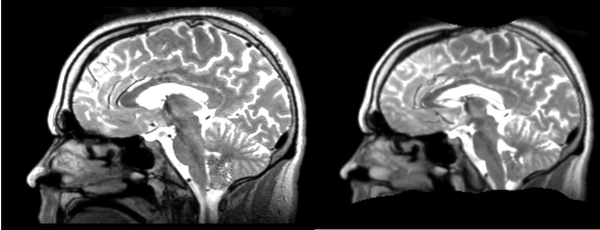

Different subject registration

In this, I'll be moving images like so:

- 01053-t2 -> 01031-t2 = Result. All the images shown have the moving image on the left, the resultant image in the middle, and the target image on the right.

Rigid

01053>01031rigid.png = not bad... different brains of different sizes, but seem to be aligned in the ventricles so output seems okay. output slightly blurry. bad initial leveling displays.

Linear

01053>01031linear.png = not bad... different brains of different sizes, but seem to be aligned in the ventricles so output seems okay.output slightly blurry. bad initial leveling displays.